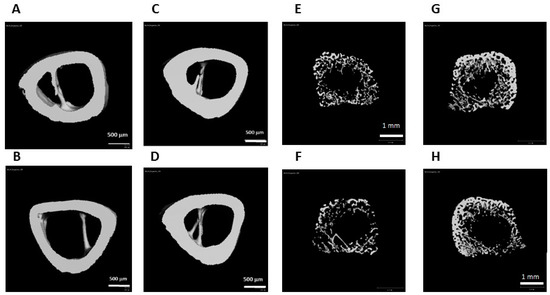

| Bone Parameters | Control 1,3 Diet (CD) (n = 8) (Mean ± SD) | Infat Oil (BPA) Diet (IO) (n = 8) (Mean ± SD) | T-Test (p Value) |

|---|---|---|---|

| Full volumetric bone mineral density (vBMD) (mg HA/cm3g) | 296.7 ± 14.85 | 306.58 ± 15.2 | 0.262 |

| (A) Cortical bone parameters | |||

| Tt.Ar (mm2) | 3.15 ± 0.07 | 3.07 ± 0.11 | 0.51 |

| Ct.Ar (mm2) | 1.75 ± 0.1 | 1.83 ± 0.12 | 0.31 |

| Ct.Ar/Tt.Ar (%) | 55 ± 0.02 | 59 ± 0.04 | 0.058 |

| Ct.Th (mm) | 0.31 ± 0.01 | 0.35 ± 0.03 | 0.026 |

| (B) Trabecular bone parameters (tROI) | |||

| BV/TV (%) | 3.9 ± 1.31 | 5.26 ± 2.02 | 0.17 |

| Tb.Th (mm) | 0.05 ± 0.004 | 0.06 ± 0.01 | 0.11 |

| Tb.N (mm-1) | 1.06 ± 0.15 | 1.19 ± 0.26 | 0.28 |

| Tb.Sp (mm) | 0.96 ± 0.14 | 0.89 ± 0.15 | 0.41 |

| (B1) Proximal ROI (proximal metaphysis) | |||

| BV/TV (%) | 5.7 ± 2 | 7.5 ± 3 | 0.22 |

| Tb.N (mm−1) | 1.46 a ± 0.2 | 1.54 ± 0.29 | 0.55 |

| Tb.Sp (mm) | 0.71 ± 0.09 | 0.69 ± 0.11 | 0.73 |

| (B2) Distal ROI (proximal metaphysis) | |||

| BV/TV (%) | 0.72 ± 0.15 | 1.25 ± 0.5 | 0.015 |

| Tb.Th (mm) | 0.05 ± 0.0 | 0.05 ± 0.01 | 0.98 |

| Tb.N (mm−1) | 0.71 ± 0.1 | 0.84 ± 0.21 | 0.154 |

| Tb.Sp (mm) | 1.42 ± 0.21 | 1.25 ± 0.23 | 0.21 |